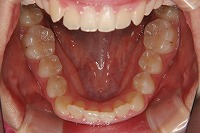

反対咬合を主訴に来院された、右側唇顎裂の10歳6ヵ月の女の子です。診断「右側唇顎口蓋裂で反対咬合を伴う」1期治療で反対咬合の解消と上顎の前歯の並びを修正しました。2期治療は抜歯をせず治療を行いました。